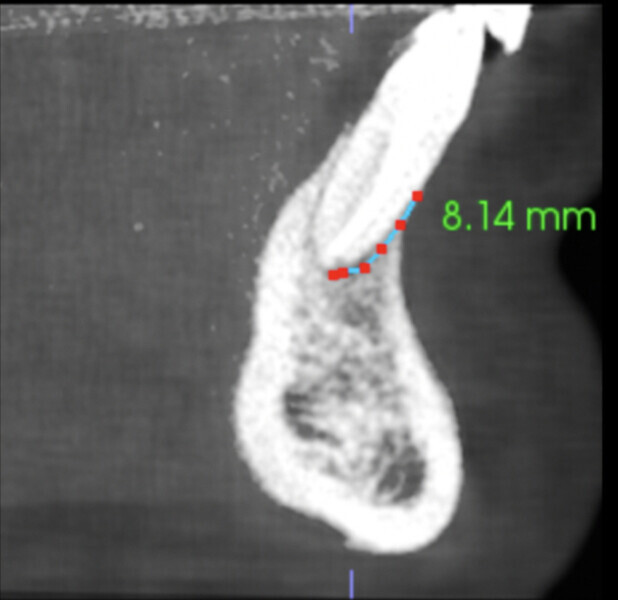

A radiograph was taken of the immediate postoperative situation and at the nine-month follow-up. Comparison showed bone apposition between the two central incisors (Fig. 4). An i-CAT scan was also taken at the nine-month follow-up to check the bone growth. The horizontal view, taken at the same level as that taken preoperatively, clearly showed the reduction of the gap from 14.11 mm to 4.42 mm at the cortical level and the trabecular bone showed the same trend in healing (Fig. 5). The vertical view showed that the bone on the buccal plate was growing towards the root and growing vertically (Fig. 6). Almost 8.2 mm in height had been regained and in direct contact with the roots of the teeth. Indeed, when provided with a scaffold on which to grow, the bone can grow in all directions, including vertically, where there was an open periodontal pocket. This is the major breakthrough of this technique. No bone grafting material or a membrane was placed. The periosteum was in great condition, and for me, it was the best membrane I could wish for.

Fig. 6b: Vertical views of both central incisors showing bone healing under the apices and bone growing vertically on the buccal aspect (b & c).

Fig. 6c.

Figs. 9a–f: Comparison of the vertical views of the i-CAT scans taken pre-op (a & b) and at the nine-month follow-up (c & d) and 18-month follow-up (e & f), showing continued growth of the bone vertically.